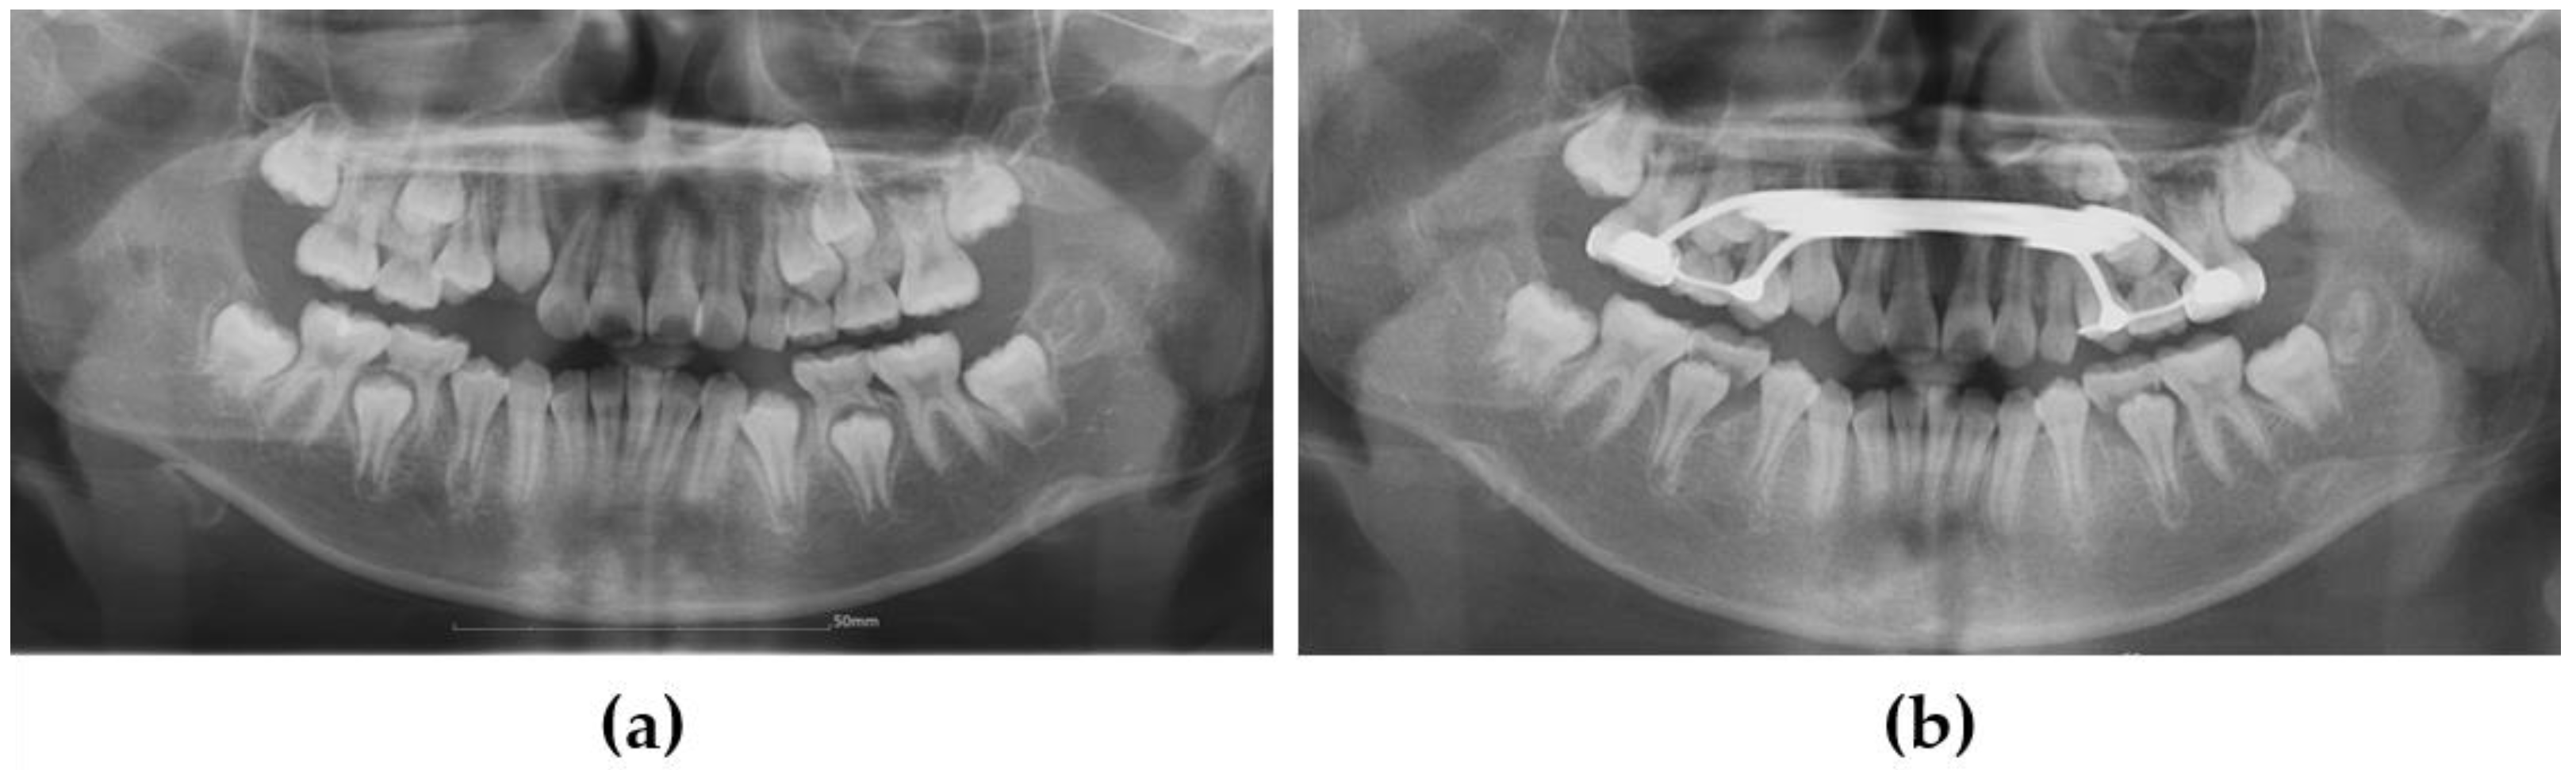

3.1. Case 1

3.2. Case 2